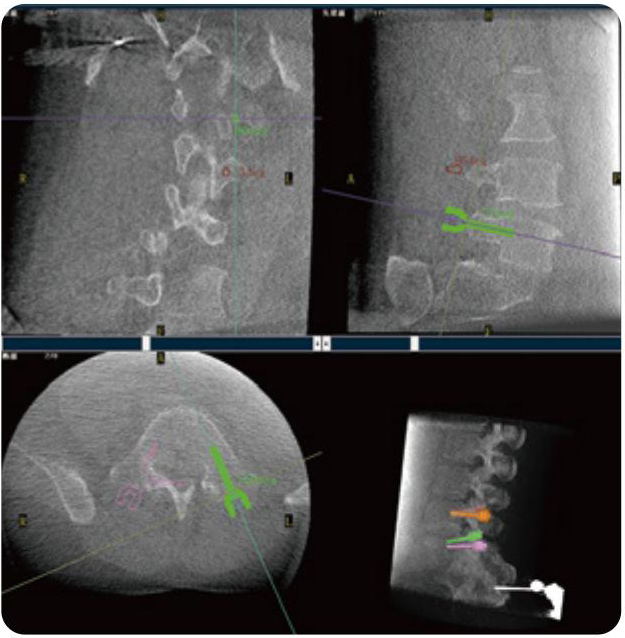

PL300B可應(yīng)用于多節(jié)段脊柱外科手術(shù),輔助醫(yī)生定位病灶部位,為脊柱外科手術(shù)(經(jīng)皮椎體成形術(shù)、椎弓根螺釘內(nèi)固定術(shù)等術(shù)式)提供術(shù)前手術(shù)流程規(guī)劃、入釘位置、角度可視化引導(dǎo),模擬仿真入釘輔助。